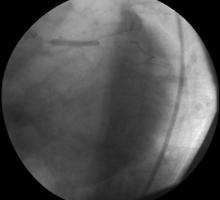

1) LMCA showed subtotal distal occlusion (Figure 1)

4) RCA was occluded from proximal part (Figure 2).